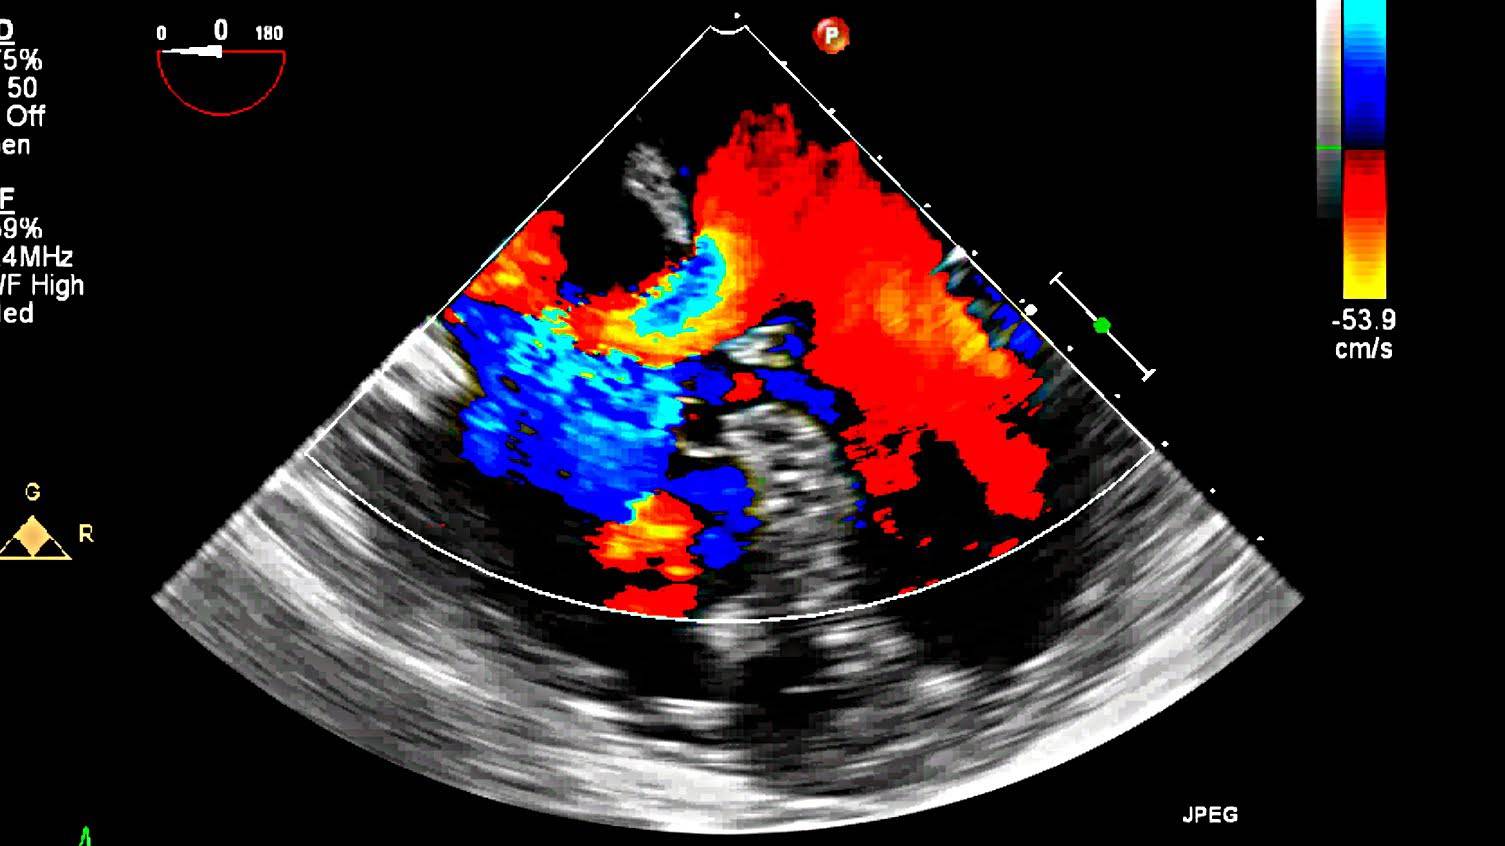

۳.اکوکاردیوگرافی داپلر (Doppler)

اکوکاردیوگرافی داپلر برای ارزیابی جریان خون در قلب و عروق جنین استفاده میشود. این روش برخلاف دو نوع قبلی که تمرکز بر ساختارهای فیزیکی قلب دارند، بیشتر به بررسی عملکرد قلب از نظر جریان خون میپردازد.

در این نوع تصویربرداری، پزشک میتواند سرعت و جهت جریان خون را اندازهگیری کند. این اطلاعات نقش کلیدی در تشخیص مشکلاتی مانند نارسایی قلبی، تنگی یا نارسایی دریچهها، و اختلالات در دهلیزها و بطنها دارد. در صورتی که پزشک به وجود ناهنجاری در گردش خون جنین مشکوک شود، استفاده از اکو داپلر بهعنوان ابزار تشخیصی الزامی خواهد بود.

اکوکاردیوگرافی داپلر: این تکنیک داپلر برای اندازه گیری و ارزیابی جریان خون از طریق اتاقک ها و دریچه های قلب استفاده می شود. داپلر همچنین میتواند جریان خون غیرطبیعی در قلب را تشخیص دهد که میتواند مشکلاتی مانند باز شدن بین حفرههای قلب، مشکل یک یا چند دریچه از چهار دریچه قلب یا مشکل دیوارههای قلب را نشان دهد.

داپلر رنگی داپلر رنگی شکل پیشرفته اکوکاردیوگرافی داپلر است. با داپلر رنگی، از رنگ های مختلف برای تعیین جهت جریان خون استفاده می شود. این کار تفسیر تصاویر داپلر را ساده می کند.